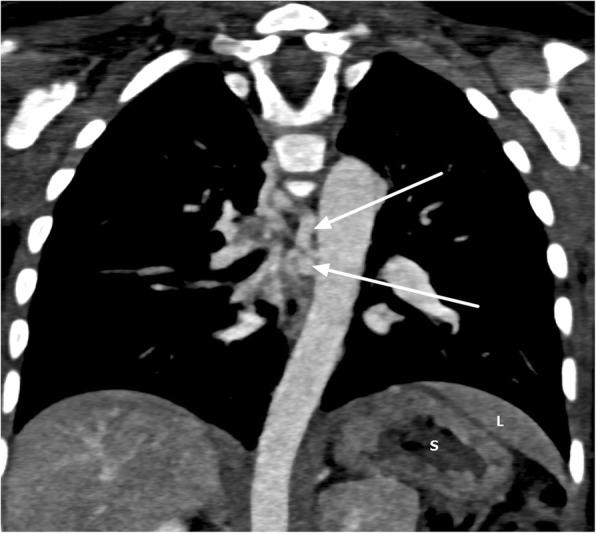

We report a case of a 31- month-old infant black girl in Tanzania who presented with an on-and-off history of difficulty in breathing, easy fatigability, facial and lower-limb swelling, recurrent respiratory tract infections, and failure to thrive.

我们报告了一名来自坦桑尼亚的31个月大黑人女婴的病例,该患儿有断断续续的呼吸困难、易疲劳、面部和下肢肿胀、反复呼吸道感染以及发育不良的病史。